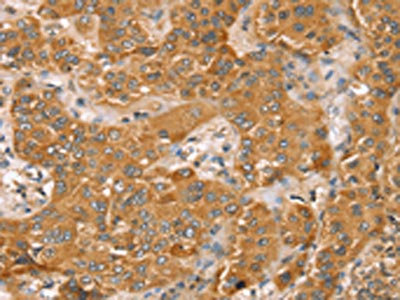

The image on the left is immunohistochemistry of paraffin-embedded Human breast cancer tissue using CSB-PA572337(TRIM45 Antibody) at dilution 1/45, on the right is treated with synthetic peptide. (Original magnification: ×200)

The image on the left is immunohistochemistry of paraffin-embedded Human liver cancer tissue using CSB-PA572337(TRIM45 Antibody) at dilution 1/45, on the right is treated with synthetic peptide. (Original magnification: ×200)